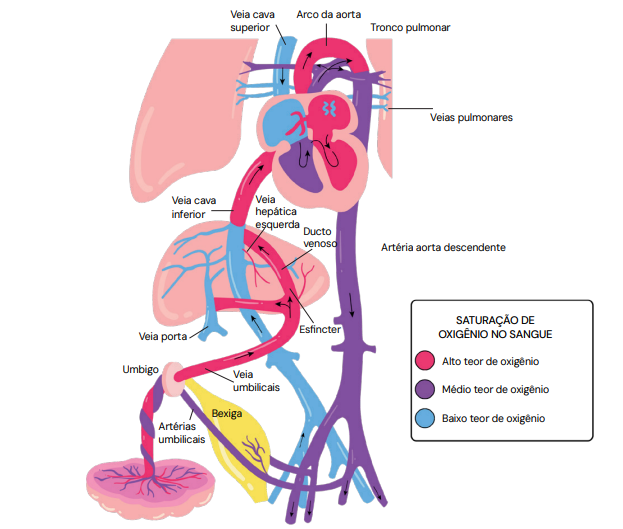

centralização fetal ou “brain-sparing”. A centralização é um mecanismo de adaptação e, isoladamente, não define sofrimento fetal. - Ducto Venoso (DV): É um dos últimos vasos a se alterar. O aumento do seu IP ou a presença de uma onda “a” ausente ou reversa indicam falência do coração direito devido à sobrecarga e se correlacionam fortemente com acidemia fetal.

A sequência de eventos hemodinâmicos é: ↑ IP da AU → ↓ IP da ACM (centralização) → ↑ IP do DV (acidemia = sofrimento fetal).